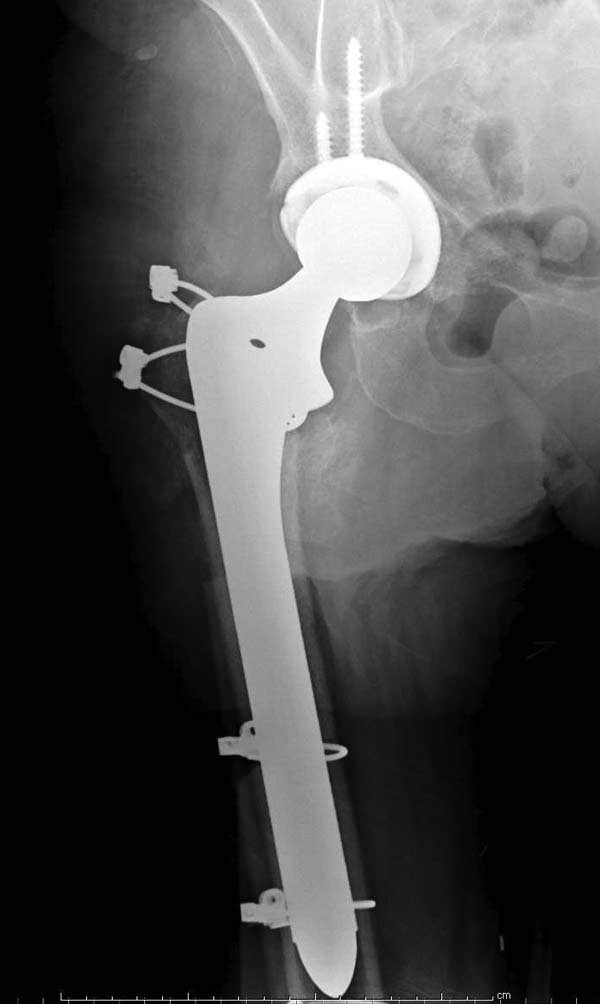

Такие “чужие осложнения” встречаются у всех и представляю банальный случай, который шаг за шагом показано как перерос в более сложный процесс... Больная 70 лет, множественные ко-морбидности, чрезвертельный перелом первоначально фиксирован Гамма 3. Осложнение в течение 6 недель, ревизия тотальной артропластикой и во время установки ножки обнаружена трещина диафиза (17), из малого доступа фиксация алло-графтом.

Обычно после чрезвертельных переломов, за исключением молодых, у пожилых остается нестабильность при движении. Часто падают и после 3х мес. в результате падения обнаружен перипротезный перелом (22-23), который зафиксирован Синтез пластиной.

Повторно поступает после двух с половиной лет, где обнаруживается перелом на второй стороне. Немного сложно, но для фиксации выбрали Antegrade InterTan Smith Nephew Nail и с момента фиксации более 3х мес.